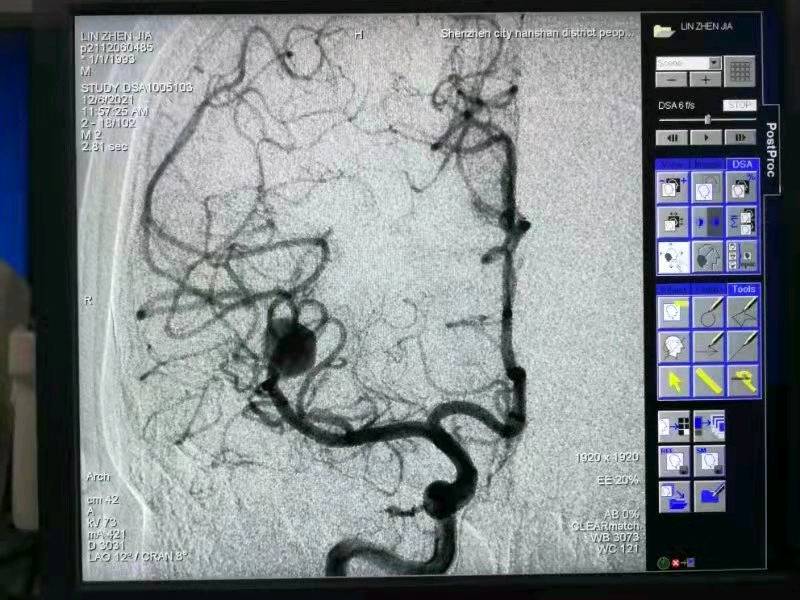

这个年轻患者在有效抗感染治疗的同时,优先处理 介入弹簧圈栓塞右侧脑动脉瘤,避免体外循环手术脑出血死亡风险。限期处理感染的二尖瓣,替换27 #St. Jude. 机械瓣,手术效果良好,术后规律抗感染治疗6周,康复出院!